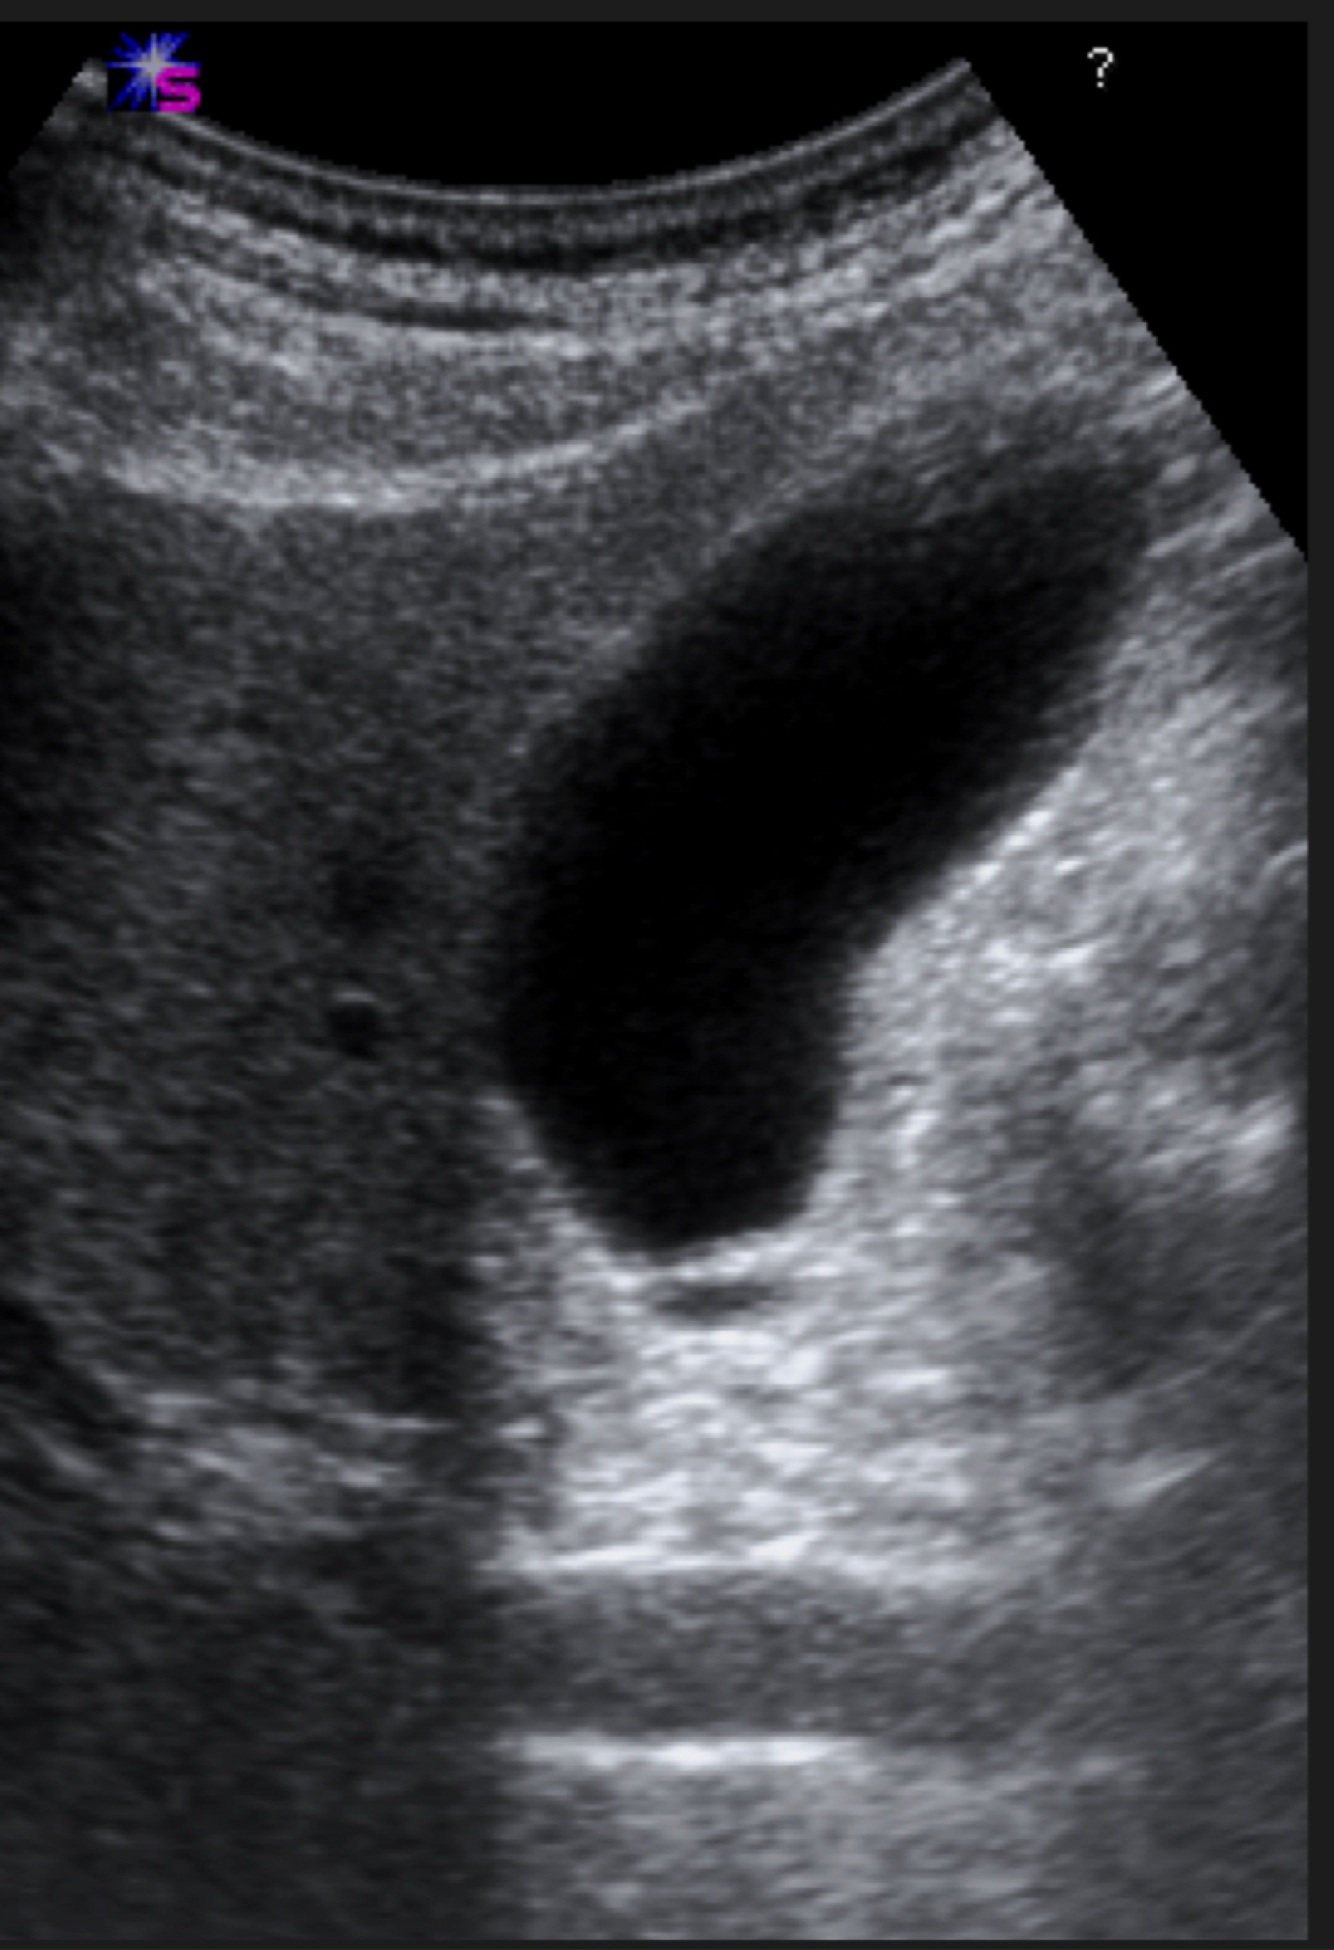

Q

Name the structure

A

Gallbladder (Ultrasound)

18

The gallbladder in ultrasound appears…

Hypoechoic